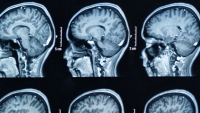

Although the diagnosis remains based exclusively on history and symptomatology, modern diagnostic techniques, particularly high-resolution magnetic resonance imaging, provides valuable new insight into the pathophysiology of these cases with additional implications for therapeutic strategies. In most cases, a compressive vessel, or less commonly a tumor or demyelinating plaque from multiple sclerosis, is clearly seen on the high resolution MRI scan.